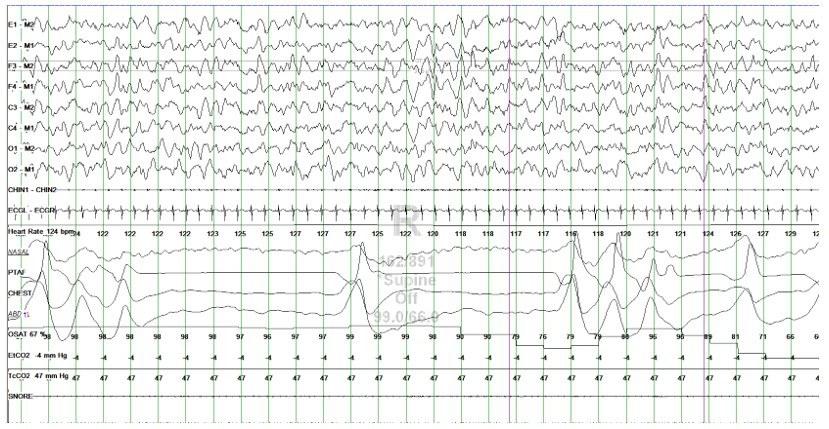

A nine month-old former 24 week preemie female twin with a history of bronchopulmonary dysplasia with hypoxemia on 0.5LPM oxygen supplementation, GERD, right grade II and left grade I perinatal intraventricular hemorrhage, neonatal hypertension, and stage II retinopathy of prematurity presents to our institution for an oxygen titration sleep study. Abnormal breathing pattern was seen during the polysomnography, and a representative 60-second epoch is pictured below.

Overall apnea hypopnea index (AHI) without supplemental oxygen was 54.9/h which reduced to 2.3/h with 0.5L supplemental oxygen. The respiratory channels showed rapid shallow breathing alternating with irregular periods of apnea lasting 7-8 seconds, and shorter pauses both associated with oxygen desaturations. As in the figure below the apnea was interrupted by single or multiple irregular breaths. This breathing pattern resolved with supplemental oxygen.